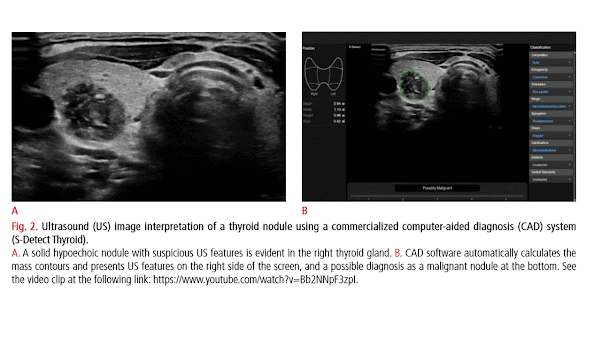

Thyroid nodules are a common clinical problem, occurring in 19%-68% of the healthy population [1-3]. Ultrasonography (US) is an essential diagnostic tool used to assess the risk of malignancy and to inform decision-making regarding the use of fine-needle aspiration (FNA) and postFNA management in patients with thyroid nodules [1-3]. However, accurate recognition and consistent interpretation of US features are challenging for less-experienced operators, resulting in moderate to substantial interobserver and intraobserver variability [4-8]. In addition to experienced radiologists, many other clinicians-including endocrinologists, surgeons, nuclear medicine physicians, cytopathologists, family practice physicians, and other non-imaging specialists-perform thyroid US at primary care centers; therefore, unnecessary FNA and/or diagnostic surgery are commonly performed, placing a significant burden on the healthcare system and causing considerable anxiety to patients [1-3]. In addition, examining thyroid nodules on US is relatively labor-intensive due to their high prevalence in practice. Artificial intelligence (AI)-based computer-aided diagnosis (CAD) systems, based on machine learning (ML) and deep learning (DL) techniques, have been introduced for thyroid cancer diagnosis  to overcome the limitations of US diagnosis by clinicians. Many studies have reported the potential roles of these systems in thyroid cancer diagnosis, and have demonstrated comparable or even higher diagnostic performance than experienced radiologists [813]. However, at this point, the use of AI tools in clinical practice is of great concern since most studies were designed as proof-of concept or technical feasibility research without a thorough external validation of real-world clinical performance [14-16]. Most studies have been based on algorithms developed by individual researchers, and only a few have investigated the use of commercially available systems. In this review, we discuss the clinical background, development, and validation studies of AI-based CAD systems in thyroid cancer diagnosis, and describe the future developmental directions of these systems for the personalized and optimized management of thyroid nodules.